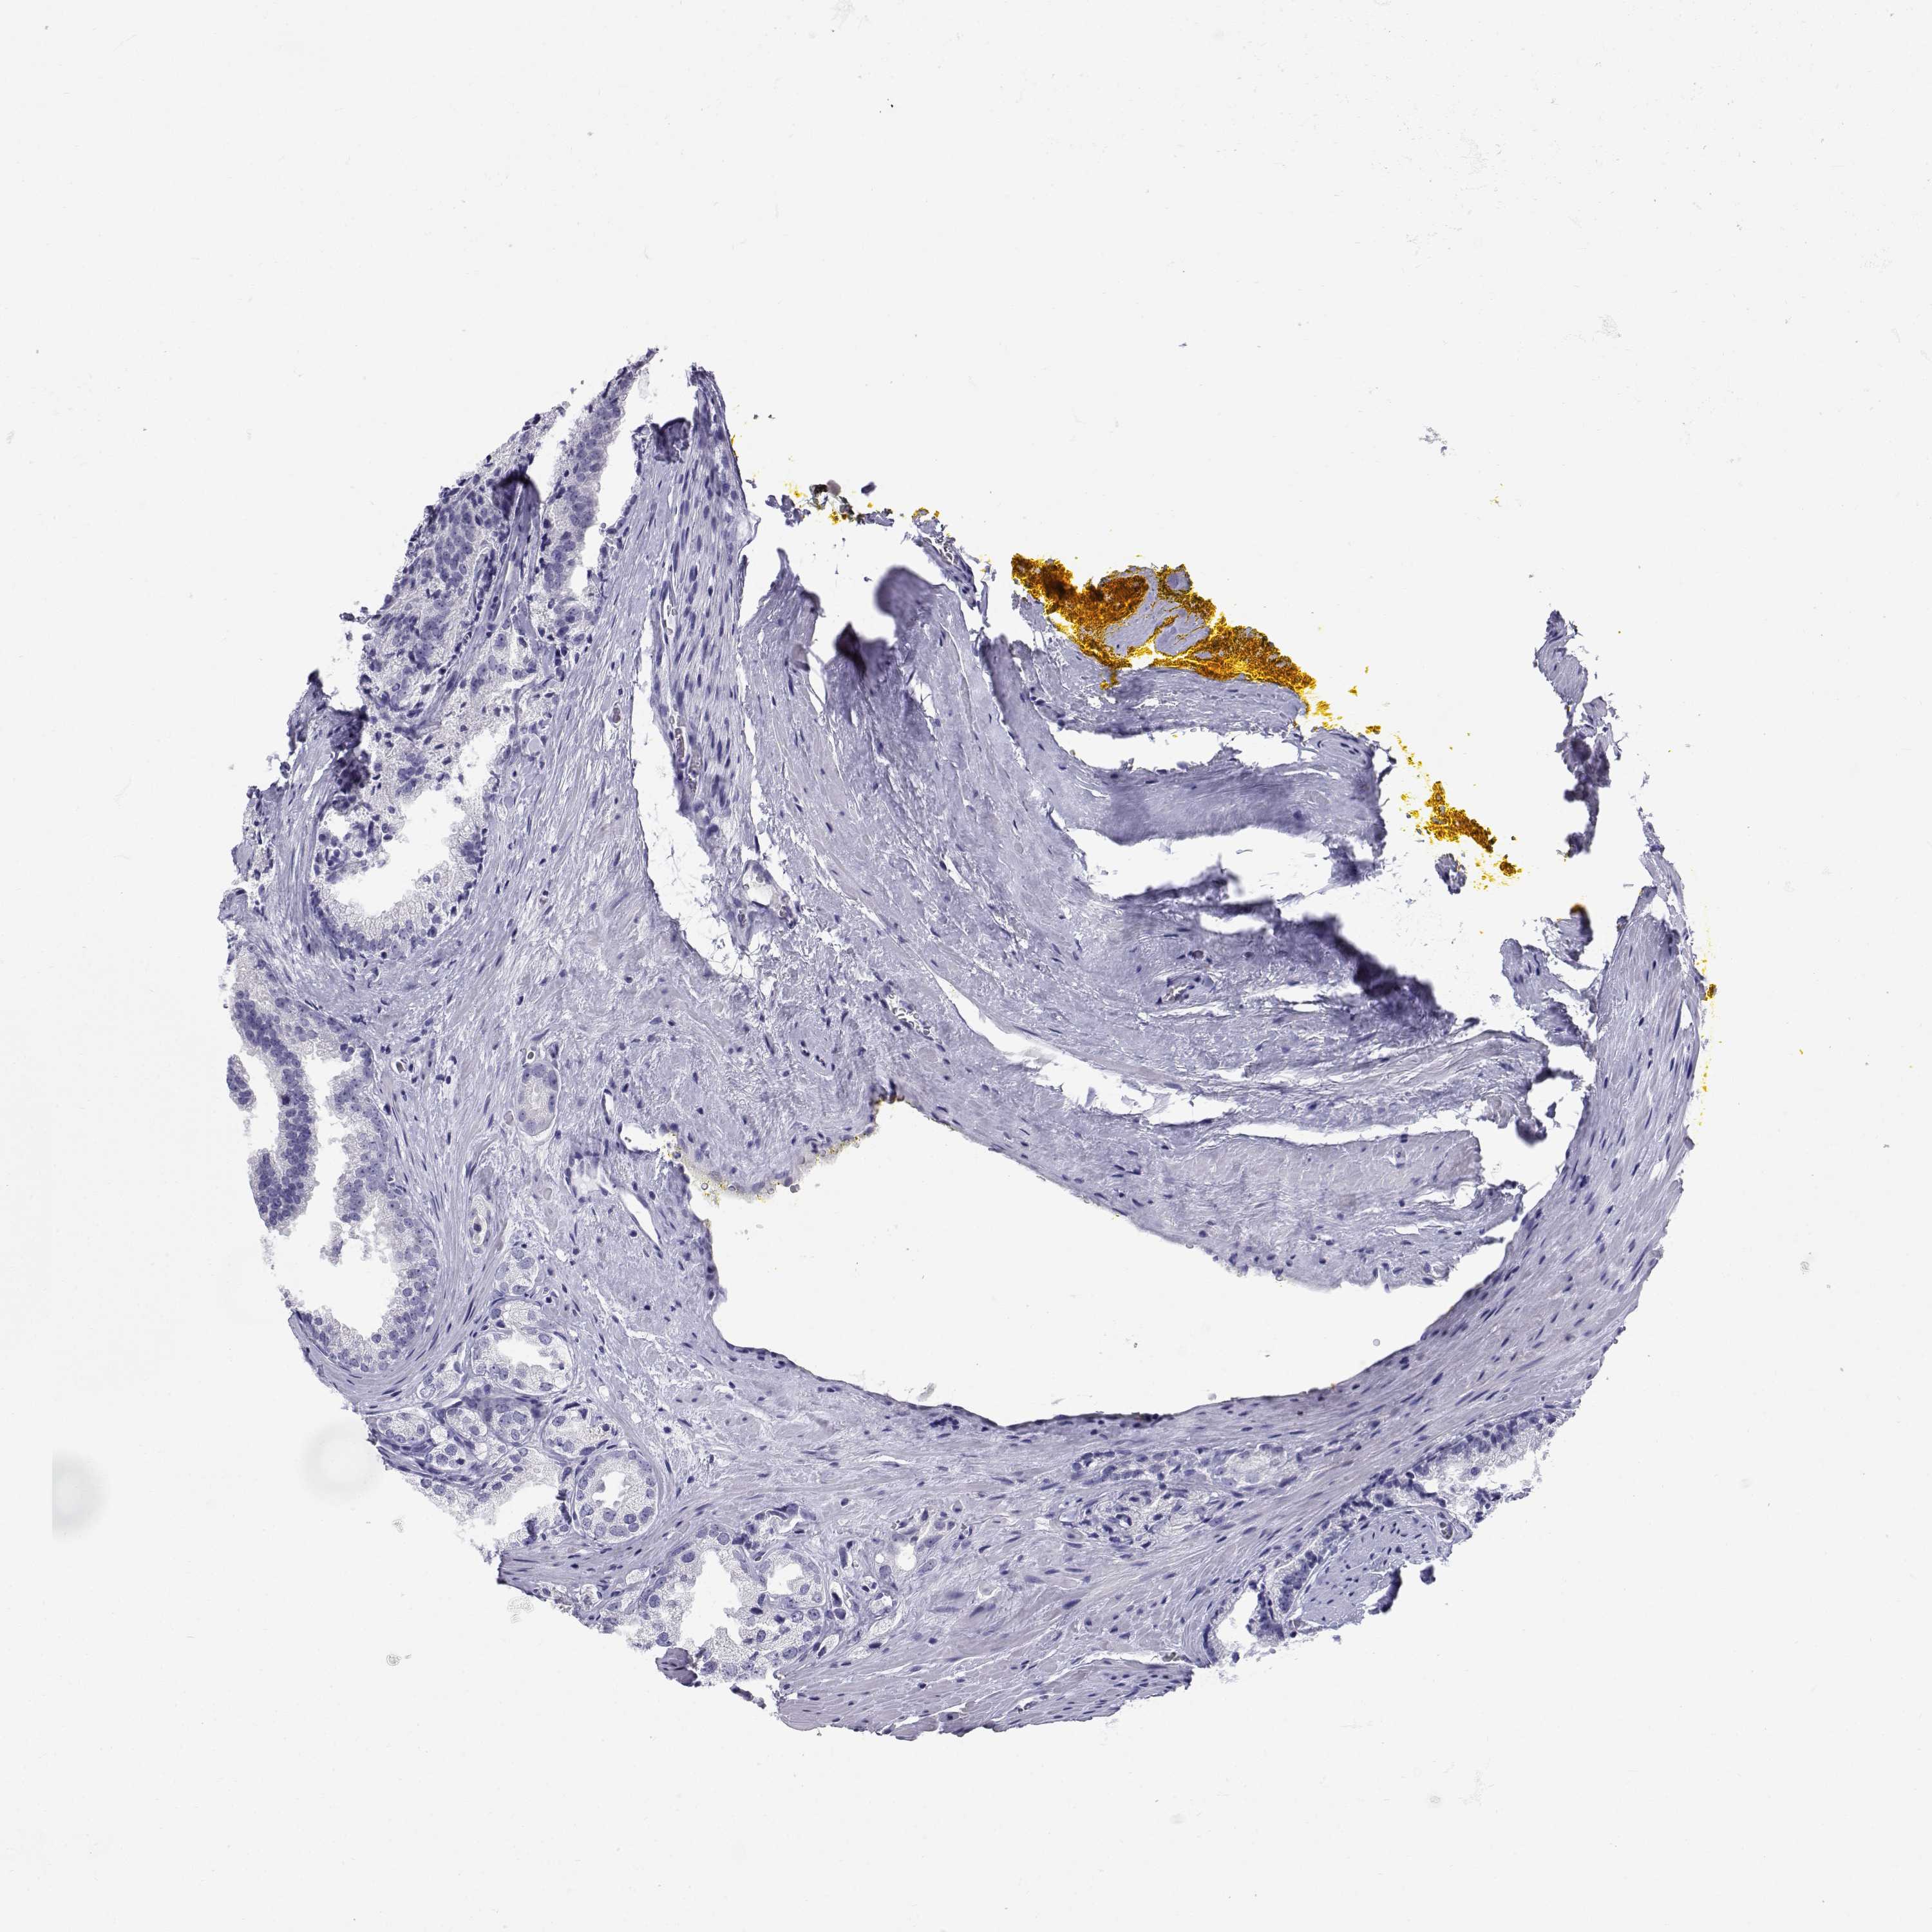

PROSTATE CANCER - Protein expressioni

A mouse-over function shows sample information and annotation data. Click on an image to view it in a full screen mode. Samples can be filtered based on level of antibody staining by selecting one or several of the following categories: high, medium, low and not detected. The assay and annotation is described here.

Antibody stainingi

Antibody staining in the annotated cell types in the current human tissue is reported as not detected, low, medium, or high, based on conventional immunohistochemistry profiling in selected tissues. This score is based on the combination of the staining intensity and fraction of stained cells.

Each image is clickable and will lead to virtual microscopy that enables deeper exploration of all samples and also displays staining intensity scores, fraction scores and subcellular localization as well as patient and tissue information for each sample.

Antibody CAB078172

Adenocarcinoma, High grade